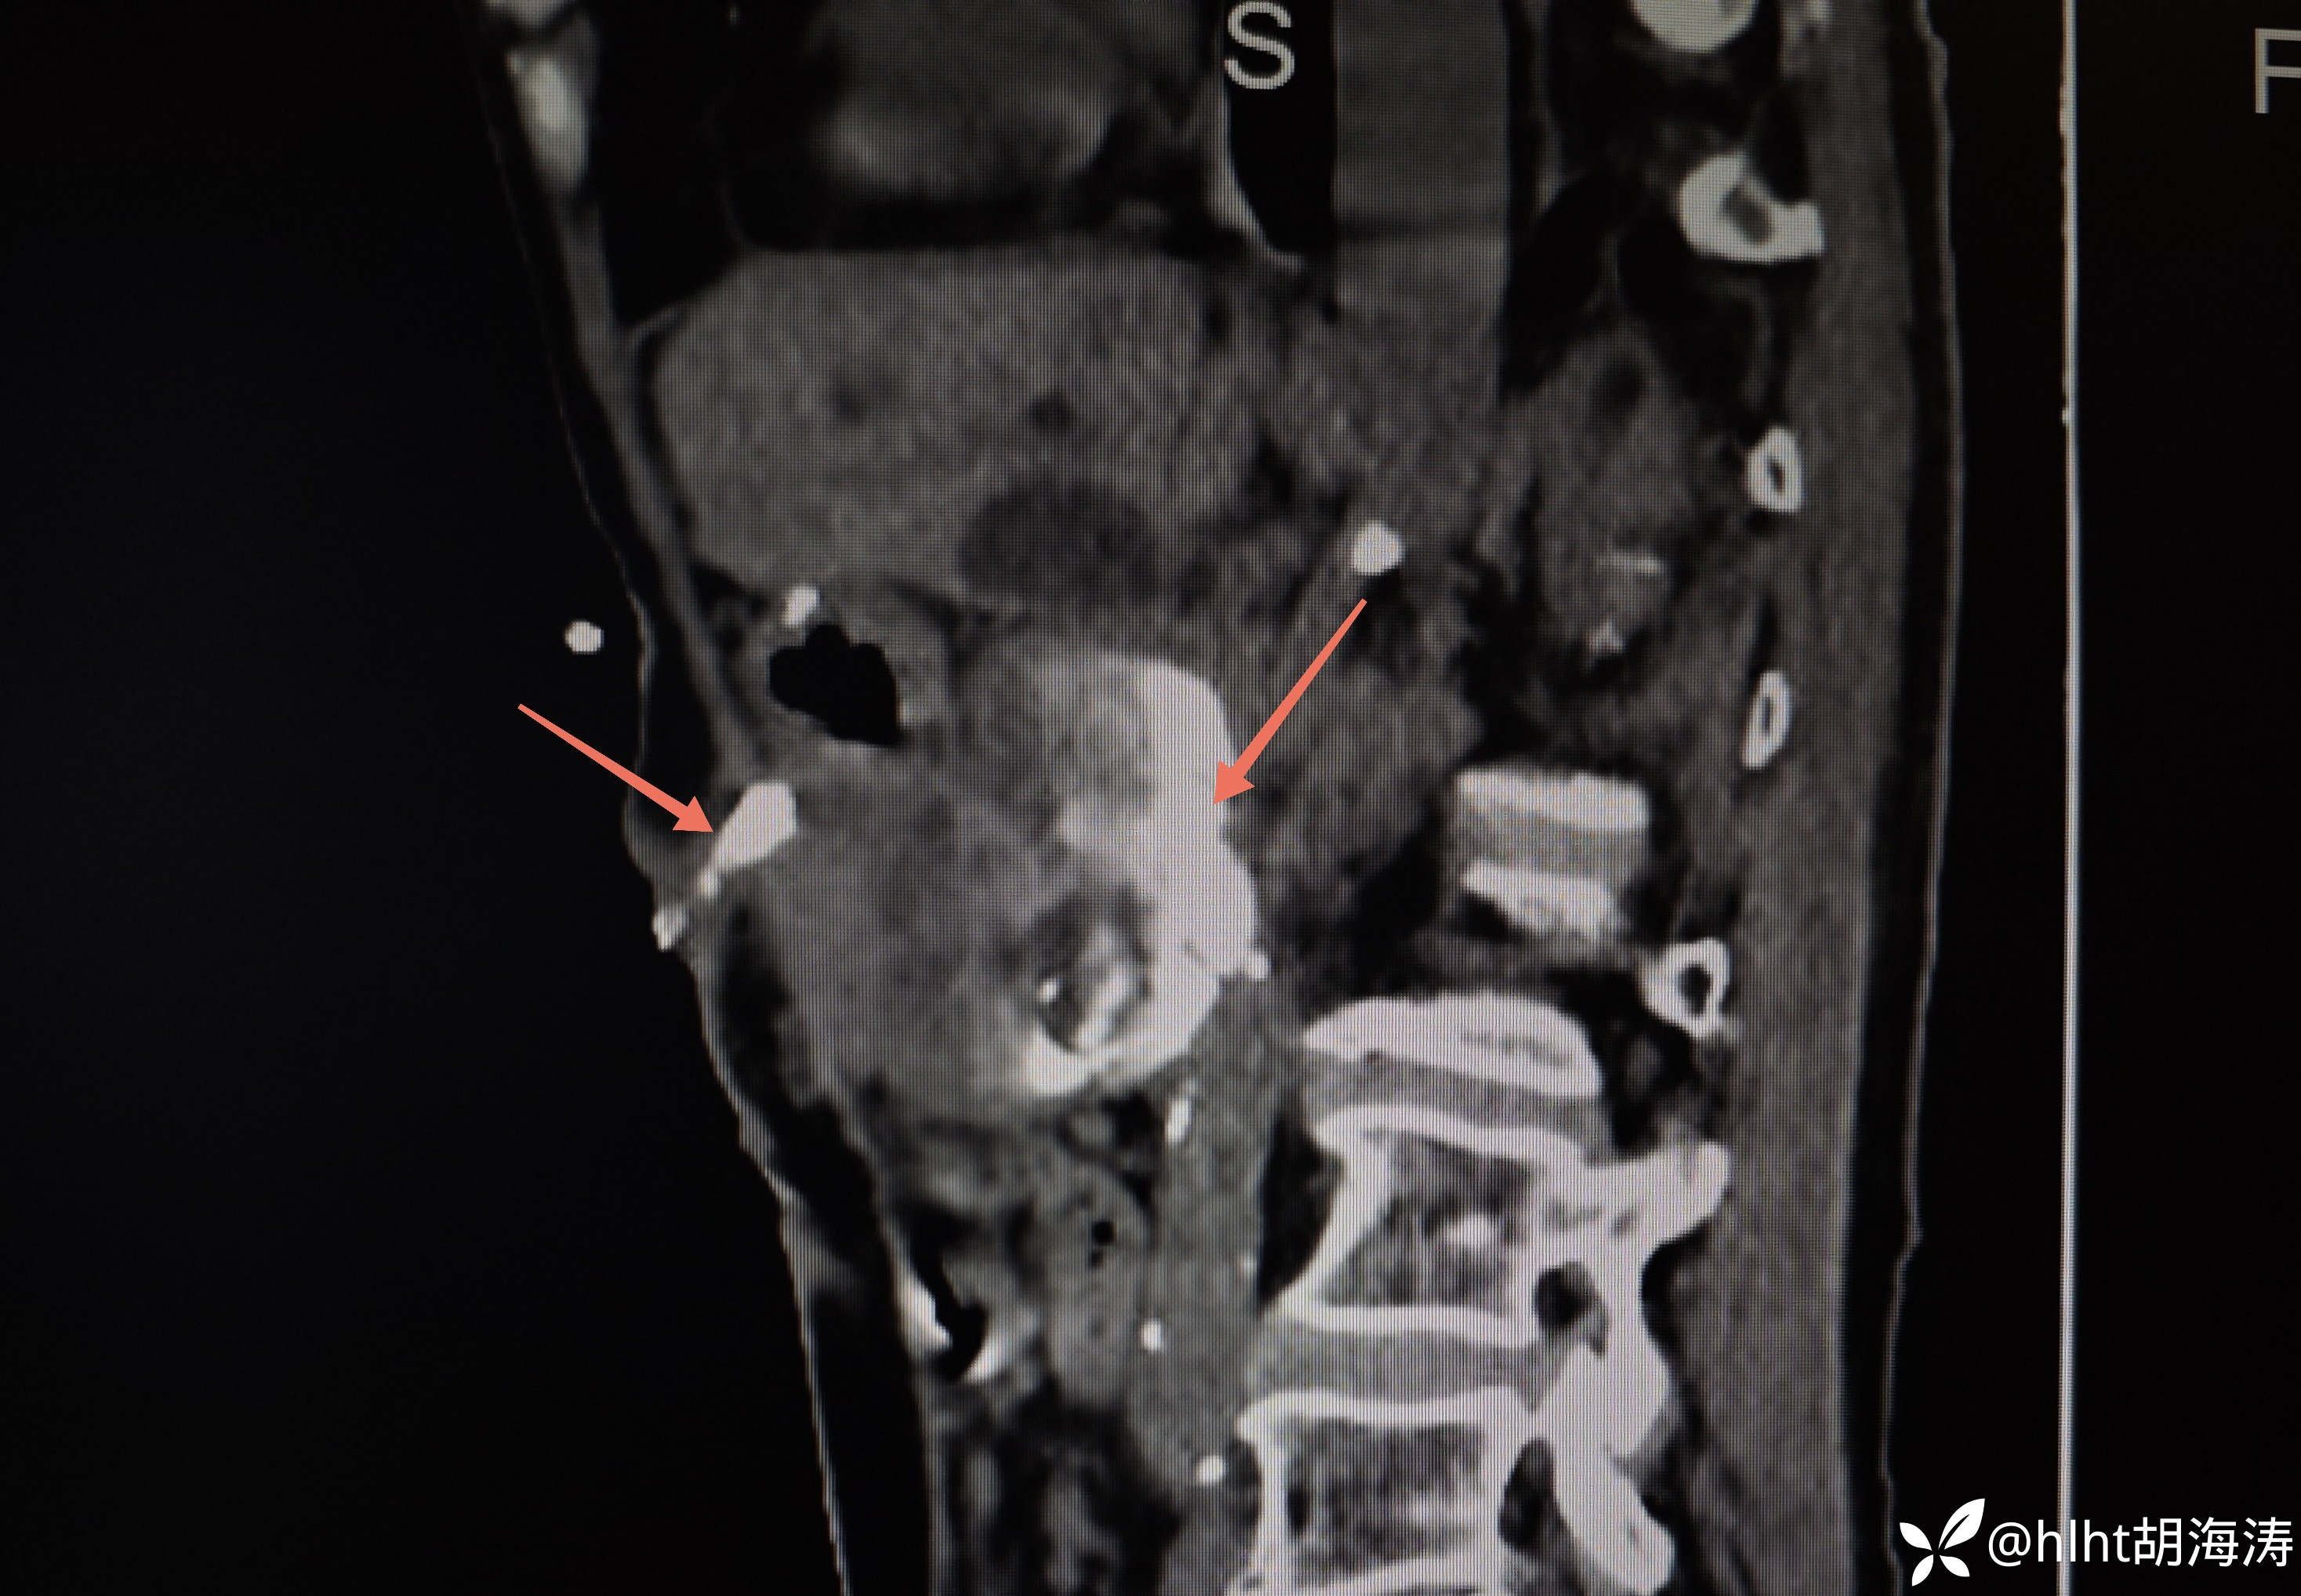

窦道CT:腹壁窦道与胆肠吻和输出袢相通

病史和分泌物淀粉酶很高,诊断胰瘘是肯定的,但手术后3年,出现胰瘘原因?与反复胆道感染是否相关?